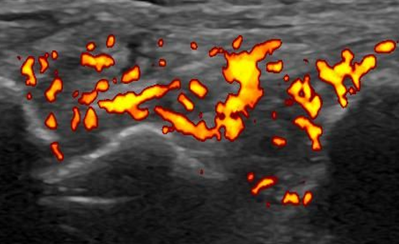

X線検査では、RAが進行すると関節周囲の骨粗鬆症に加えて、関節裂隙の狭小化、骨びらん、強直などがみられます。しかし、RA発症の初期(図1、図3)ではこうしたX線の変化はほとんどみられません。関節エコー検査(図2)やMRI検査(図4)を用いるとX線検査では認めることのできないRAの早期の変化である活動性滑膜炎や骨びらんを確認することができるので、RAの早期診断と早期治療につながります。

当院では、毎月1回(土曜日)にリウマチ専門医による関節エコー外来を実施しています。

関節エコーは、関節リウマチの早期診断や治療効果の評価に有用な検査です。 - 全身疾患であるリウマチ膠原病疾患の臓器合併症に対応